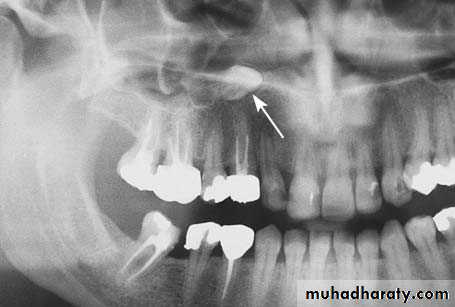

Radiograph showing impacted maxillary canines. Right canine is located labially while left canine is located palatally

Radiograph showing impacted canine with a labial localization, which is in contact with the anterior wall of the maxillary sinus

Radiograph showing impacted maxillary canines with a palatal localization